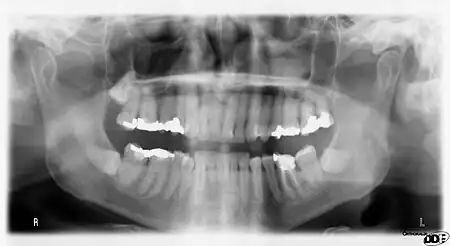

Usually, there are 20 primary ("baby") teeth and 32 permanent teeth, the last four being third molars or "wisdom teeth", each of which may or may not grow in. Among primary teeth, 10 usually are found in the maxilla (upper jaw) and the other 10 in the mandible (lower jaw). Among permanent teeth, 16 are found in the maxilla and the other 16 in the mandible. Each tooth has specific distinguishing features.

Teeth are named by their sets and also arch, class, type, and side. Teeth can belong to one of two sets of teeth: primary ("baby") teeth or permanent teeth. Often, "deciduous" may be used in place of "primary", and "adult" may be used for "permanent". "Succedaneous" refers to those teeth of the permanent dentition that replace primary teeth (incisors, canines, and premolars of the permanent dentition). Succedaneous would refer to these teeth as a group. Further, the name depends upon which arch the tooth is found in. The term, "maxillary", is given to teeth in the upper jaw and "mandibular" to those in the lower jaw. There are four classes of teeth: incisors, canines, premolars, and molars. Premolars are found only in permanent teeth; there are no premolars in deciduous teeth. Within each class, teeth may be classified into different traits. Incisors are divided further into central and lateral incisors. Among premolars and molars, there are first and second premolars, and first, second, and third molars. The side of the mouth in which a tooth is found may also be included in the name. For example, a specific name for a tooth may be "permanent maxillary left lateral incisor."

There are several different dental notation systems for associating information to a specific tooth. The three most commons systems are the FDI World Dental Federation notation, Universal numbering system (dental), and Palmer notation method. The FDI system is used worldwide, and the universal is used widely in the United States.